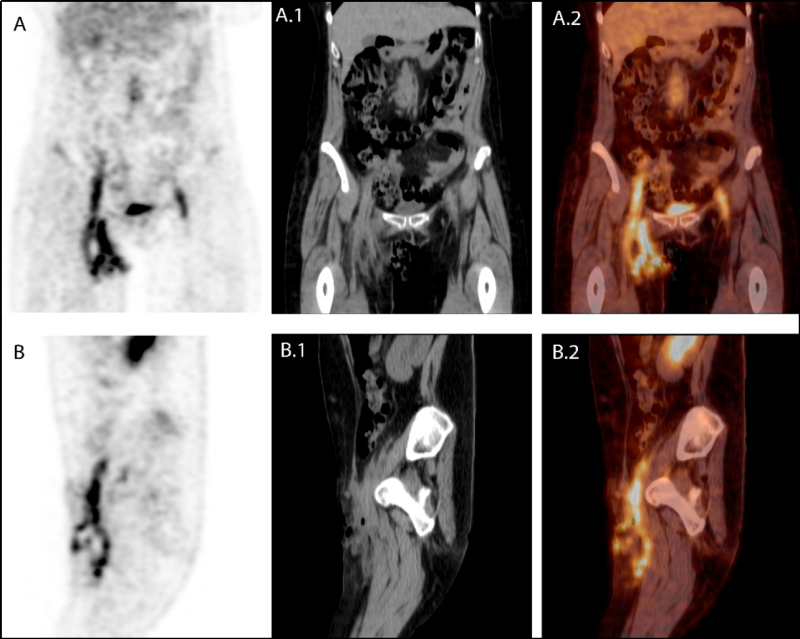

A fin de valorar la extensión de la infección y la posible afectación del by-pass, se realizó en primer lugar una angio-TC donde se evidencia permeabilidad del by-pass y líquido libre periprotésico en su vertiente distal derecha que conecta con la colección inguinal derecha de aproximadamente 1,8 x 3,8 cm. Posteriormente se realiza PET/TC con 18F-FDG a los 120 min de la administración IV de 160 MBq de 18F-FDG que muestra un intenso consumo lineal, homogéneo y difuso en todo el trayecto protésico, sugestivo de infección del mismo (figs. 1 y 2).